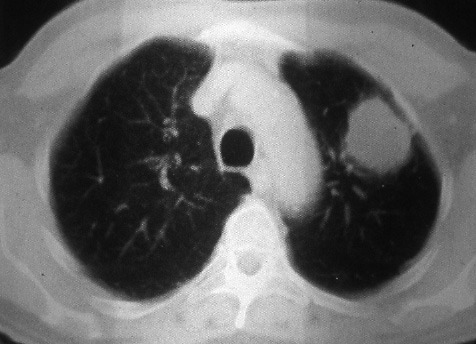

Fig. 36b: Computed tomographic scan of the lesion in Fig. 36a. The visceral pleura was not involved.